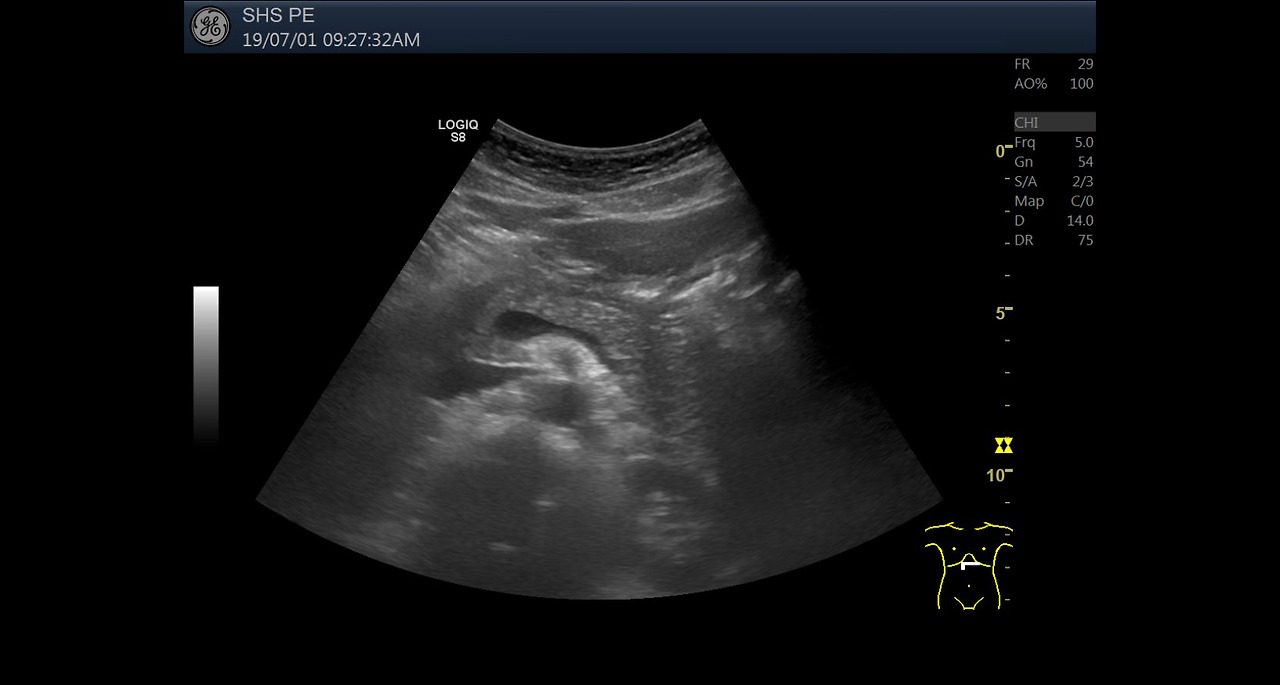

복부 초음파 검사는 인체의 복부 내 장기들을 실시간으로 확인할 수 있는 비침습적 영상 진단 방법입니다. 고주파 음파를 복부 피부에 쏘아 내부 장기의 반사 신호를 영상화하는 기술로, 내시경이나 CT와는 달리 방사선 노출 없이 안전하게 검사할 수 있다는 장점이 있습니다.

복부 초음파 검사 절차

- 검사 전 금식 안내 및 확인

- 초음파 젤을 복부에 도포

- 초음파 프로브(탐촉자)를 이용해 장기 확인

- 검사 중 환자의 자세 변경 요청 가능

- 검사는 약 10~20분 내외 소요

- 영상 촬영 후 의료진이 결과 판독

검사 중 통증은 없으며, 비침습적 방식이기 때문에 특별한 부작용이나 위험 없이 누구나 받을 수 있습니다.